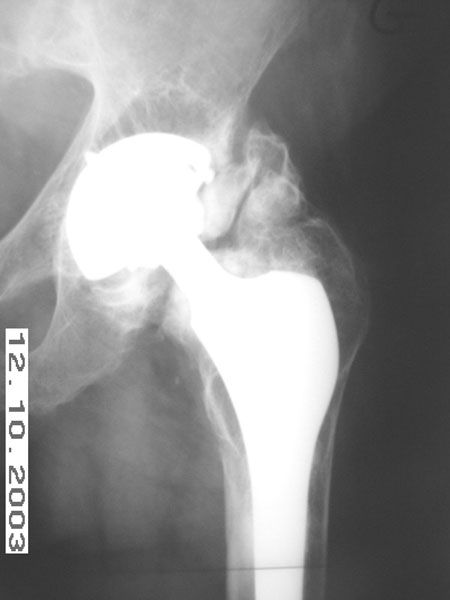

Mise au point Les ossifications péri prothétiques, la complication (un peu trop ?) oubliée , L. Vastel Centre Hospitalo-Universitaire Cochin Port-Royal Assistance Publique - Hôpitaux de Paris N°143 - Avril 2005 ● 16 min de lecture